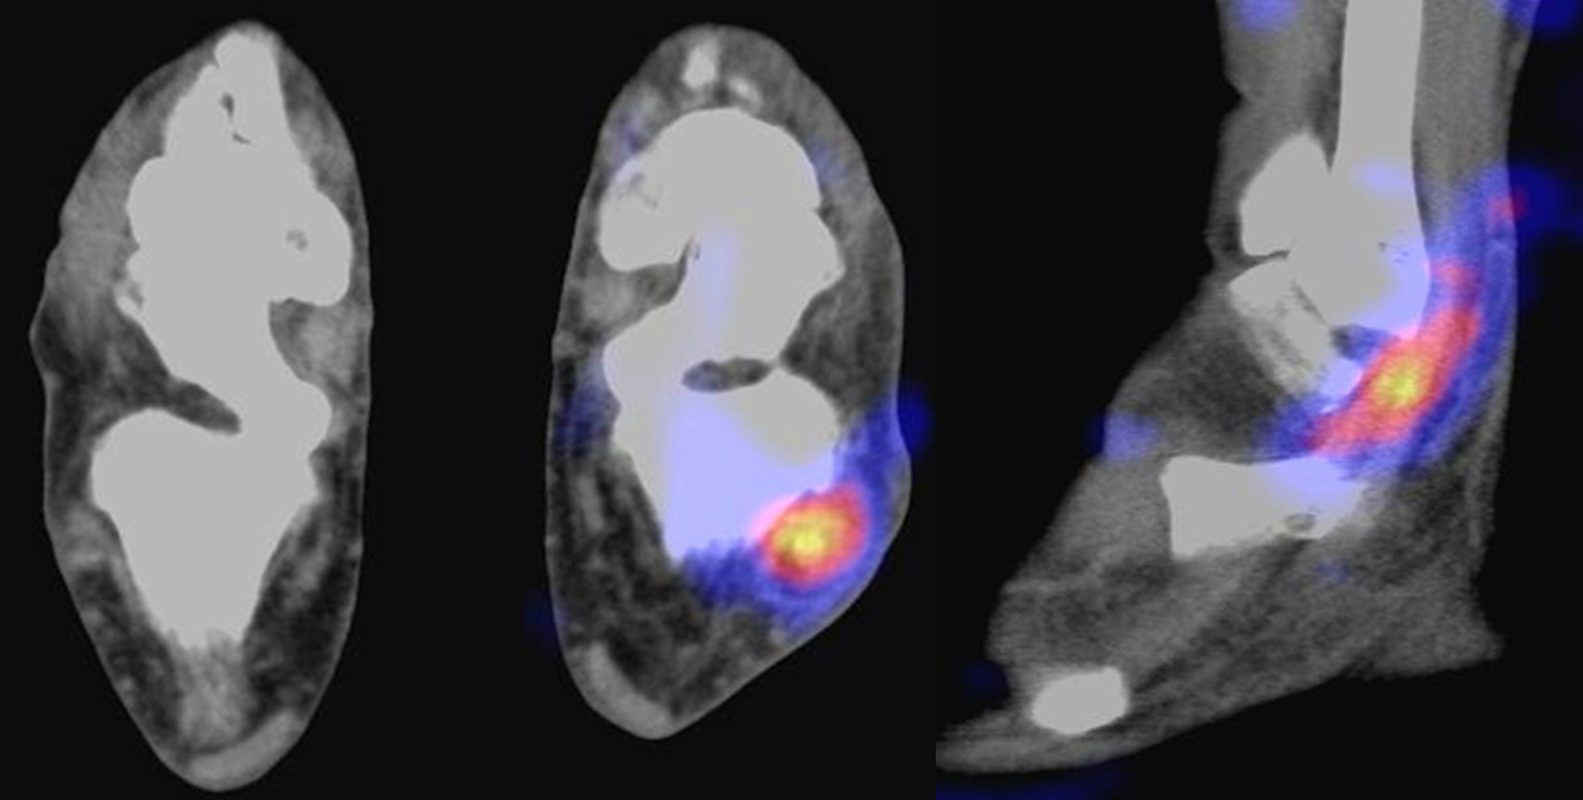

Abbildung 2.1.

Bildbeispiele symptomatische OCL

Zum Lesen der Bildbeschreibung und zur Vollansicht bitte das Bild anklicken. Bild: H. C. Rischke

Abbildung 2.2.

Bilder eines Patienten mit Z. n. mehrfachen Sprunggelenksdistorsionen in der Vergangenheit, besonders heftige Distorsion des linken Sprunggelenkes 5 Wochen vor der Untersuchung. Die SPECT/CT zeigt eine instabile osteochondrale Läsion mit deutlicher Aktivierung.

Abbildung 2.3.

Klärung bei Schmerzen im rechten OSG bei OCL an der medialen Talusschulter. Z. n. OSG-Distorsion vor 2 Jahren und Z. n. OSG-Fraktur / Syndesomosenruptur. Ausgedehnte OCL, hier jedoch kein erhöhter Knochenmetabolismus; lediglich Nachweis einer Stressreaktion im Bereich der Synchondrose eines Os trigonum als Schmerzursache.